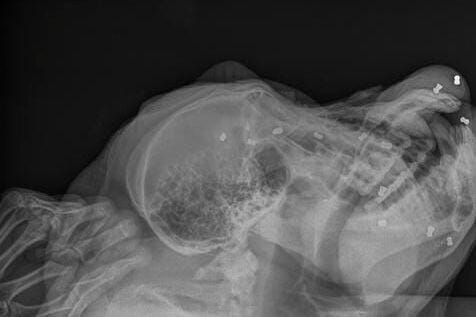

2. Sebanyak 24 peluru bersarang di tubuh Paguh, kedua matanya buta

Upaya penyelamatan Paguh dilakukan sejak Kamis (28/11). Dari hasil pemeriksaan ada 24 peluru senapan angin bersarang di tubuh Paguh.

Dari hasil pemindaian sinar x, 24 peluru itu tersebar di sejumlah bagian tubuh Paguh. Rinciannya, 16 peluru dibagian kepala, 4 di bagian kaki dan tangan, 3 di daerah panggul dan 1 peluru di daerah perut.

“Kita telah mengeluarkan tiga peluru dari bagian kepala. Perawatan intensif akan terus kami berikan kepada Paguh sampai kondisinya membaik,” rinci Meuthya.